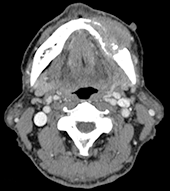

図❸ 下顎左側歯肉部から下顎骨にかけて、骨破壊を伴う腫瘤形成を認める